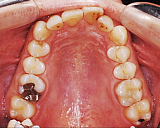

初診時の状態です。上下の歯並びがガタガタしており、奥歯の咬み合わせも正しくありません。

デーモンシステムという名前の装置を使用しています。